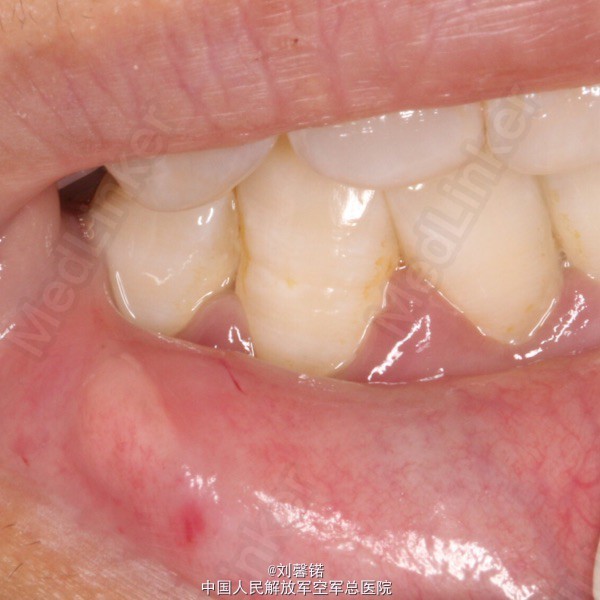

王某,男11岁 主诉:右侧下唇肿物半年余 现病史:半年来,右侧下唇近口角处一光亮“水泡”,肿胀消退,但不久又可复发,今日来我科要求治疗。

检查:右侧下唇近口角处一约花生米大小,呈半透明的无痛小疱,突出下唇表面,表面光滑,无蒂,挤压不可消失

诊断:唇黏液腺囊肿 处置:Nd激光切取,病理检查